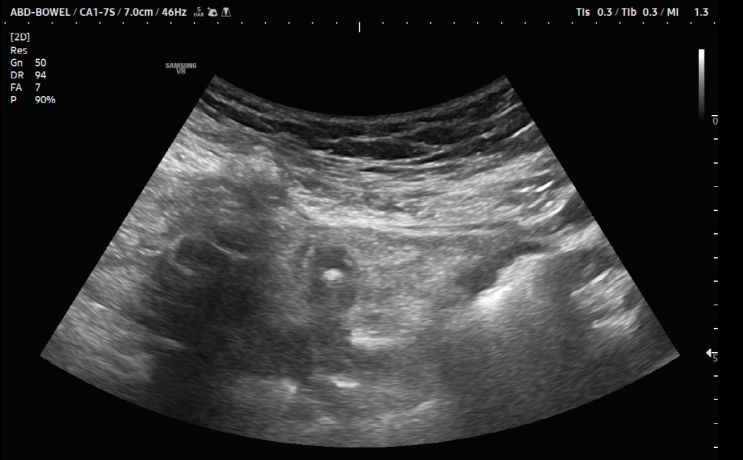

[상왕십리내과 게실염] 서울으뜸내과, 복통으로 진단된 게실염 증례

#게실염 #서울으뜸내과 #왕십리내과 #상왕십리내과 #게실 안녕하세요? 서울으뜸내과입니다. 점심시간에 증...